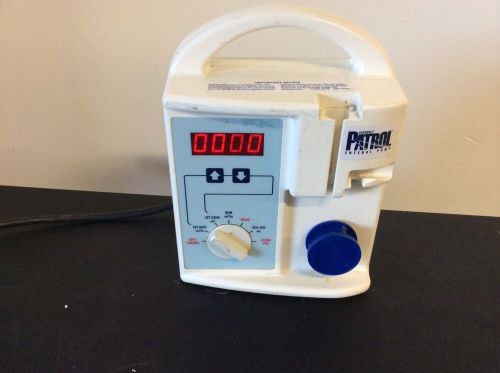

Ross Flexiflo Patrol Enteral Nutrition Pump- EXCELLENT WORKING CONDITION

(30) Abbott PATROL Enteral Nutrition Sets with Piercing Pin 52040 APR-2015 - NEW